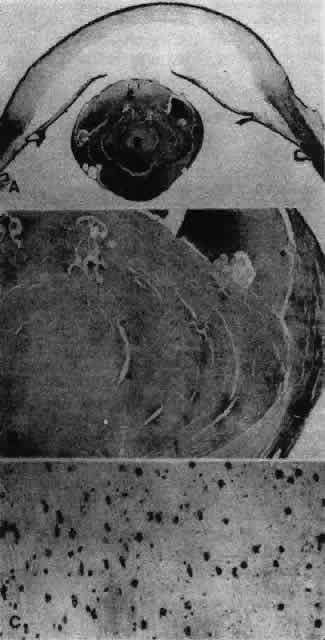

Other opacities that fall under the category of capsulolenticular cataracts are the polar cataracts. In this case, the opacities are situated at either pole of the lens and generally involve only the superficial cortical area. The relatively common anterior variety assumes a number of forms but is typically plaquelike and circumscribed. The size of the opacity may vary from a small dot to one that occupies the entire pupillary region. Because it may have a laminate appearance, it has also been called a pyramidal cataract. Similar opacities are observed in children who have had corneal ulcers during infancy. The fact that the fetal nucleus of the lens is not involved suggests an occurrence relatively late in intrauterine life. Occasionally, an opacity might be seen above the previously incurred derangement separated by an apparently normal lenticular zone, producing the so-called reduplicated cataract. In this case, it is believed that, following an initial disturbance, normal fibers are deposited, followed later by a new, sometimes more severe disturbance that produces a second region of opacification. There are a number of variations on this theme, and such opacities may assume myriad possible forms. It may be significant that these opacities are often associated with a strand or strands of pupillary membrane that bridge the iris (in the region of the collarette) to the polar cataract.181–183 Similar adhesions to the pupillary margin have been noted. Another observation has been that these cataracts are often associated with signs of keratitis, most notably corneal opacification. It is interesting that, histologically, the changes are similar to those observed in the adult human lens following corneal ulceration.177–180 The polar cataract is typically associated with a hyperplasia of the epithelium and a great deal of necrosis of lens fibers in the subepithelial area.184 Multistratification of the epithelium occurs as the cells fill a depression left by the necrotic fibers (Figs. 36 AND 37). The cells become spindle-shaped and produce PAS-positive material. Contrary to a long-held but erroneous notion, the plaque thus formed does not represent a metaplastic transformation of epithelial cells into fibroblasts.185 The plaque is often undermined by normal cuboidal epithelial cells and is eventually surrounded by capsulelike material (see Figs. 36 AND 37). The most reasonable explanation of the basis of this anomaly is the development of intrauterine inflammation. Although it has been suggested that the anterior polar cataract may be the result of a persistent vascular tunic that interferes with nutrition, the counterpart, the posterior polar cataract, need not be associated with hyaloid remnants, yet the histologic picture is quite similar.

Fig. 36. Photomicrographs of the development of anterior subcapsular cataract. A. The beginning of multistratification of the anterior epithelium, owing to localized hyperplasia of the lens epithelial cells. B. Further stratification of the epithelium, with denucleation occurring in some of the cells. C. The final stage of cataract formation showing the so-called fibrous plaque (F), bounded on the anterior and posterior sides with capsule material. Beneath the posterior capsule (C) a newly formed epithelial population can be seen (E). (Yanoff M, Fine BS: Ocular Pathology. New York, Harper & Row, 1975)

Among capsulolenticular cataracts are the misnamed congenital anterior and posterior “capsular” cataracts. These are cataracts, the nomenclature notwithstanding, that are associated not with the capsule per se but with the underlying substrata. This rare aberration is usually found in conjunction with remnants of the vascular tunic and generally does not cause a loss of vision. In the case of anterior capsular cataract, the main defect seems to be localized within the lens epithelium, the underlying fibers being transparent and unaffected. Biomicroscopically, the opacity consists of small flecks or dots of a white or bluish tint. The posterior capsular cataract does not involve the capsule or underlying fibers but consists primarily of spindle-shaped epithelial cells.158 Two primary hypotheses have been advanced to explain the appearance of these congenital anomalies. One suggests that they are the result of an intrauterine inflammation.176 This is consistent with an observed migration of epithelium during intraocular inflammation in adult lenses.177–180 Another equally plausible suggestion holds that the persistence of the vascular tunic interferes with the normal nutritional supply to the lens.